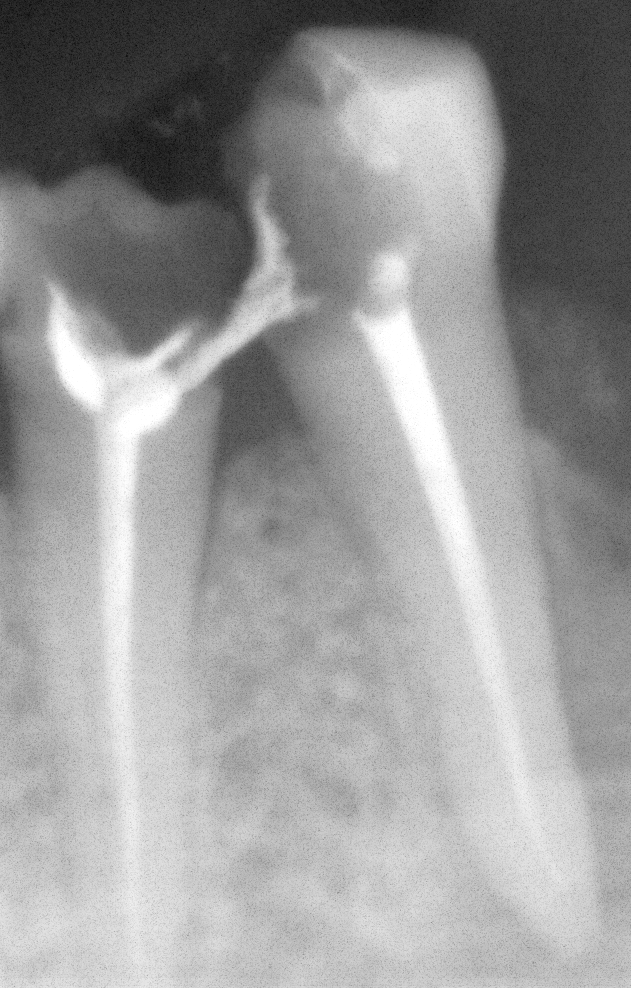

ROOT CANAL DONE BY GERMAN DENTIST FAILED (IMPROPER ROOT CANAL OBTURATION)

Re treatment of the same done at cheema dental

Before After